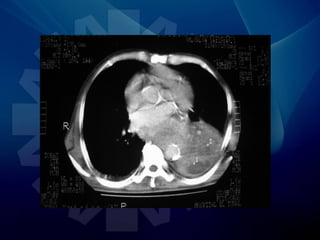

• TAC

Similar al TAC